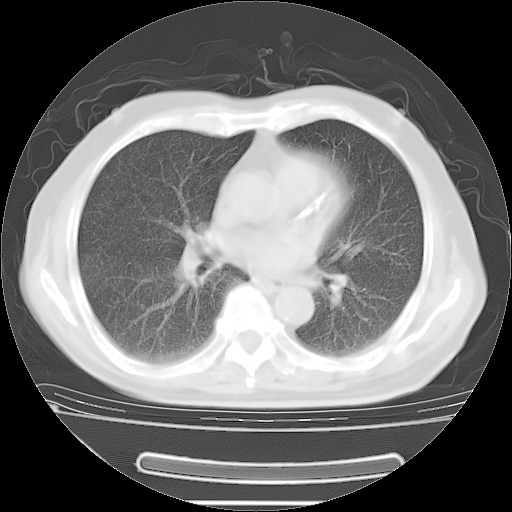

今天复查肺部CT,发现双肺广泛磨玻璃样改变。所以我把3月19日和5月9日相隔50天的肺部CT上传。请大家会诊。

5月9日肺部CT(在4月27日齐鲁医院肺部CT描述部分肺组织磨玻璃样改变,12天后肺组织广泛磨玻璃样改变)

2009年5月9日肺部CT

大致读了系列胸部CT:纵隔窗无明显异常,肺窗:从4、27至今:主要是双肺中下野外带可见毛玻璃样改变,目前处于急性肺泡炎阶段,至于原因考虑1、结替组织或胶原血管性疾病所致?2、恶性疾病如恶组在肺部所致的表现或细支气管肺泡癌?3、药物或其它原因如肺蛋白沉着症所致肺泡炎目前不太可能?总之,明天就去请我院的呼吸科、感染科、血液科和临免专家会诊哈。